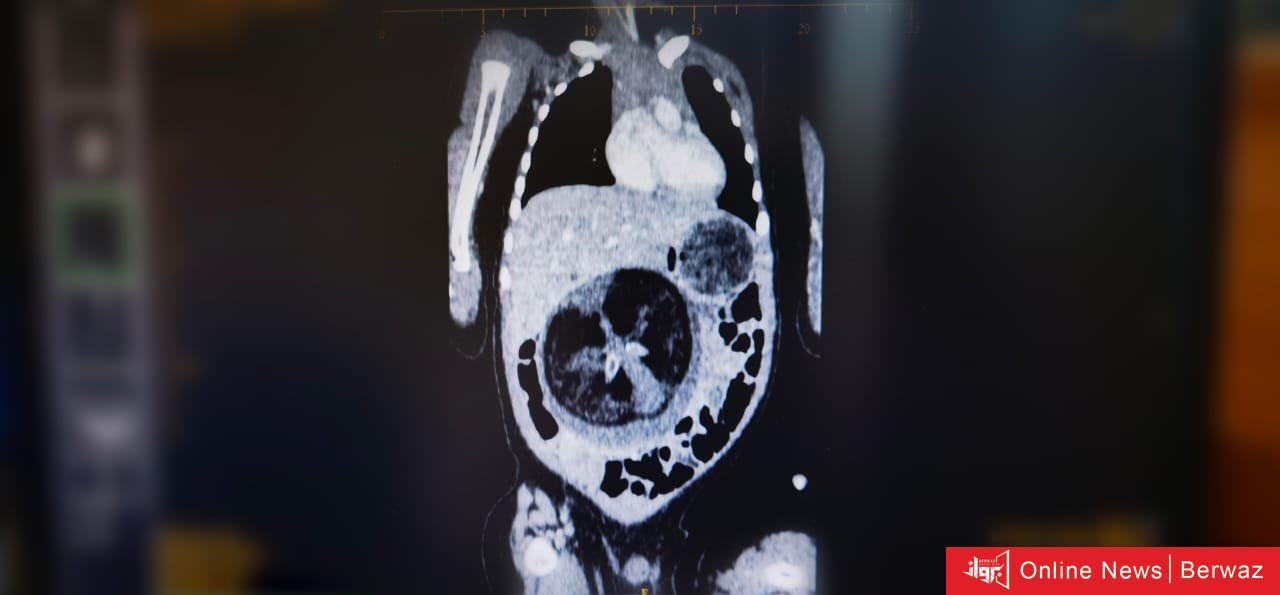

تمكن قسم جراحة الأطفال بالمستشفى السلطاني في سلطنة عمان من إجراء عملية جراحية نادرة تمثلت في استئصال جنين من داخل جنين لطفل يبلغ من العمر ثمانية أشهر، وتعد تلك الحالة نادرة الحدوث عالميًا

وتعرف هذه الظاهرة الطبية بـ Fetus in Feto، وتحدث بنسبة 1 بين كل 500 ألف حالة ولادة حية على مستوى العالم.